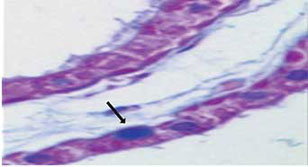

Se realizan los siguientes estudios encontrando los hallazgos a continuación reportados. Los estudios de imagen realizados durante su evolución fueron resonancia magnética de cráneo (RMN) de 0.5 UT donde solo se identificó atrofia cortical difusa, sin ningún otro hallazgo (figura 2); así como electroencefalograma (EEG) con previa colocación de electrodos mediante el sistema internacional 20-20, el cual, realizado con deprivación de sueño, mostró ritmo de fondo delta entremezclado con theta, identificando durante el trazo ondas agudas occipitales y paroxismos generalizados de polipuntas. El tamiz metabólico ampliado fue normal y el resultado de la biopsia de piel de regiones axilares identificó cuerpos de inclusión intracitoplásmicos PAS positivo a nivel de células epiteliales de glándulas sudoríparas, identificando los cuerpos de Lafora (figura 3).

Los cuerpos de Lafora fueron descritos en 1957 por Rodrigo Lafora, quién encontró inclusiones esféricas en el cerebro, aunque también se encuentran en otros órganos como músculos, hígado y en las células mioepiteliales apócrinas de las glándulas sudoríparas. Las biopsias de piel se reportan con alta sensibilidad y especificidad, observando los cuerpos de inclusión con PAS-positivo indicativo de contenido moderado de carbohidratos y que están compuestos de fibras cortas de 50-100 Armstrongs en un diámetro de 150-300. Las fibras o gránulos son muy densas en el centro de los cuerpos de Lafora.9